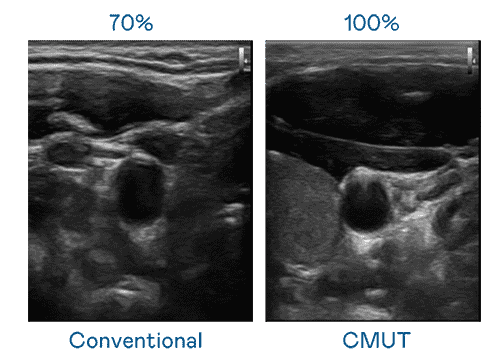

CMUT 技术是一种用电容式微机电元件来产生超音波讯号的技术。。与传统 PZT 压电式技术相比,,CMUT 频宽增加 30%,,,更宽频的超音波讯号让影像解析度大幅提升,,,,是实现高影像品质医疗超音波扫描、、、促进精准医疗发展的关键技术。。。

大频宽带来超清晰影像

超音波影像的解析度高低,,首先取决于探头能发出的讯号频宽。。。。牛牛游戏 CMUT 可提供高清晰的超音波讯号,,,提供高频宽、、、、高灵敏度、、影像纹理细节更高的超音波影像,,,协助医护人员缩短影像判读时间及利用精准的医疗影像进行诊断。。。